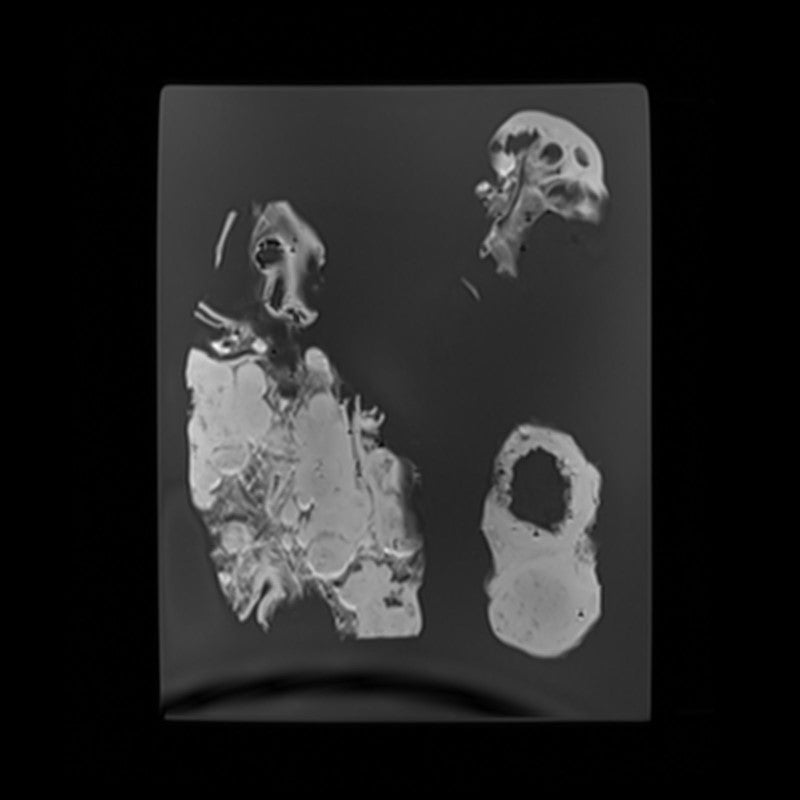

Kidney - Calculous Hydronephrosis